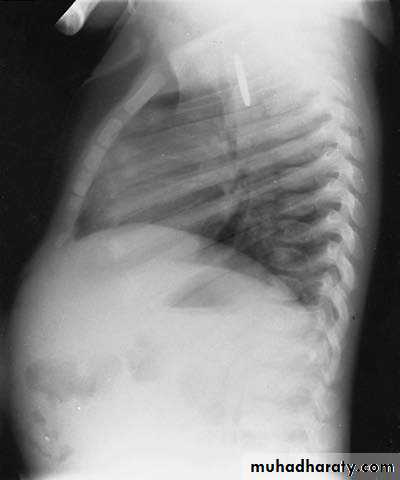

Diagnosis: achalasia cardia

Presentation:• Hailtosis

• Vomiting (not projectile)

• Wheezing

• Chest infection

Ba-swallow dilatation of esophagus with narrowing of lower part.

Treatment cardiomyotomy